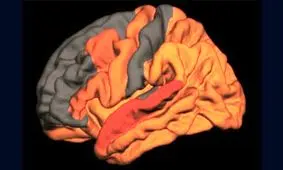

محققان در تحقیقات اخیرشان دریافتهاند که عملکرد کبد نقش اساسی در شروع بیماری آلزایمر ایفا میکند.